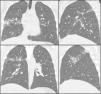

Clinical CaseThe patient was a 33-year-old male, with features of Andean ethnicity, from Guayaquil, Ecuador, who had lived in Spain since 2003. That year, on the basis of constitutional symptoms, haemoptysis, and infiltrates with cavitation in the upper lobes, tuberculous disease was confirmed at another Centre by sputum positive for Mycobacterium tuberculosis. He was admitted to a specialized Centre for 6 months of treatment: isoniazid, rifampicin, pyrazinamide, and ethambutol for 2 months, and then isoniazid and rifampicin for 4 more months. After this, the patient had periodic check-ups at another Centre, where he was reported to be asymptomatic since 2003, with the exception of rusty sputum. In 2007, in the course of this follow-up, he had a CAT scan that showed a medium-walled, 2-cm peripheral cavity with images suggestive of cylindrical bronchiectases in the posterior segment of the right upper lobe. Laboratory tests on that date showed a moderate eosinophilia of 9%. Subsequently, in 2008, when he came to our clinic for persistent rusty expectoration (which the patient described as “blood” amounting to about 5-10mL/day), a chest X-ray was taken, the findings of which were superimposable on those of the 2007 CAT scan (Fig. 1). Serial sputums were negative for acid-alcohol resistant bacilli and Löwenstein negative; a Brevundimonas vesicularis was isolated from one of them, for which the patient was started on eradicating treatment with ciprofloxacin 750mg every 12h for 21 days, but the rusty expectoration did not subside. In view of the persistence of symptoms, another chest CAT scan was done, with findings identical to those of the 2007 CAT scan (Fig. 1), and in view of the persistent mild haemoptysis presumably due to bronchiectases and localized cicatricial tracts, and the decision was made to perform a right upper lobectomy, based on normal respiratory function studies.

From a radiographic standpoint, this late phase may be entirely normal (20%) or it may present with 1 or several annular cystic peripheral lesions of variable size and wall thickness; these may be accompanied by linear peripheral tracts, which are the tunnels for movement.3,5 Localized masses or nodules may also be found, as well as thickening of the pleura adjacent to these lesions.3,5